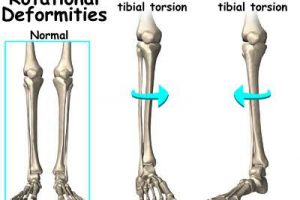

膝が痛いと当然歩き方も変わります。

また、平地を歩いている時は、通常身長の1.5%くらいは上下に体が動くのですが、ひざ痛になると、この上下運動がほとんど起きません。

地面からの衝撃を上手く吸収するためにも、この上下移動が自然にできることはとても大切です。